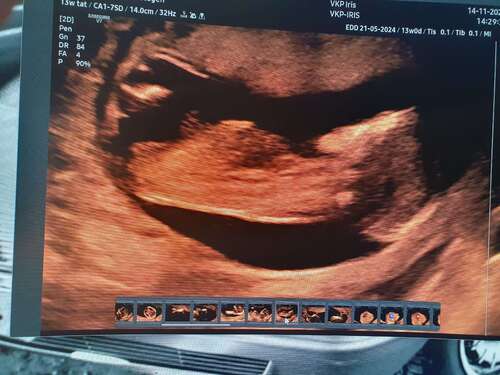

Ah kijk nu snap ik hem denk ik🙈 precies 13 weken. Hoop dat deze goed is om ...

Deze is wel erg vaag. En de blaas lijkt niet vol en niet goed te zien.

Maar ik gok een meissie 💕